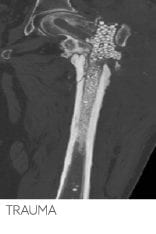

Transform infected trauma

Patient presented with: infected femoral nail and non-union of left femur with persistent discharging wounds proximally and distally.

Outcome: At 7 months follow-up there was a complete healing of the non-union and at 1 year patient remains infection free, walking with no pain.